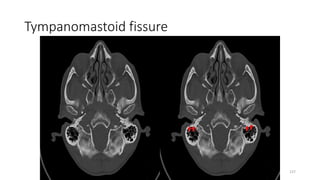

Tympanomastoid fissure

TYMPANO MASTOID FISSURE